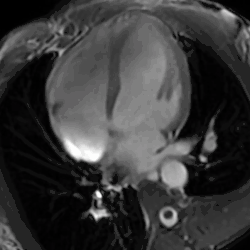

- Cardiac MRI - In athlete's heart, there is balanced atrioventricular remodeling, reduced thickening of the heart after detraining, no late gadolinium enhancement, low to normal T1 signal, and normal extracellular volume.[25]